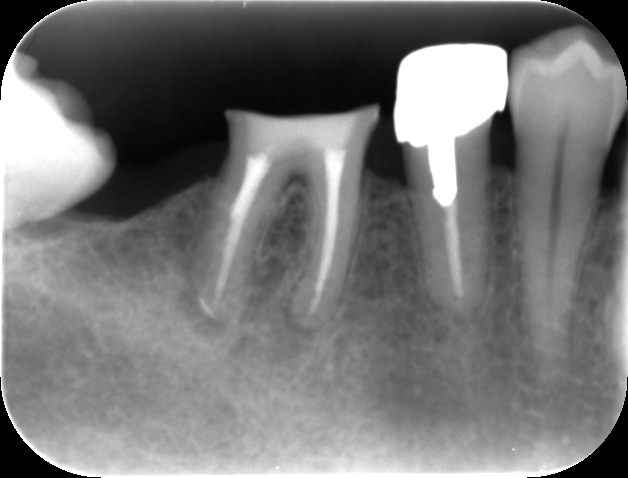

根管治療中。古い根管充填剤(白く写っている薬)と取り除き、近心根にあったファイル破折片を超音波にて除去した。これで根管の先端まで完全に清掃・消毒することが出来る。

根管充填後。症状緩解後、バイオセラミックシーラーとガッタパーチャポイントによる根管充填を行った。歯根の先端までしっかりと根管充填されているのが分かる。